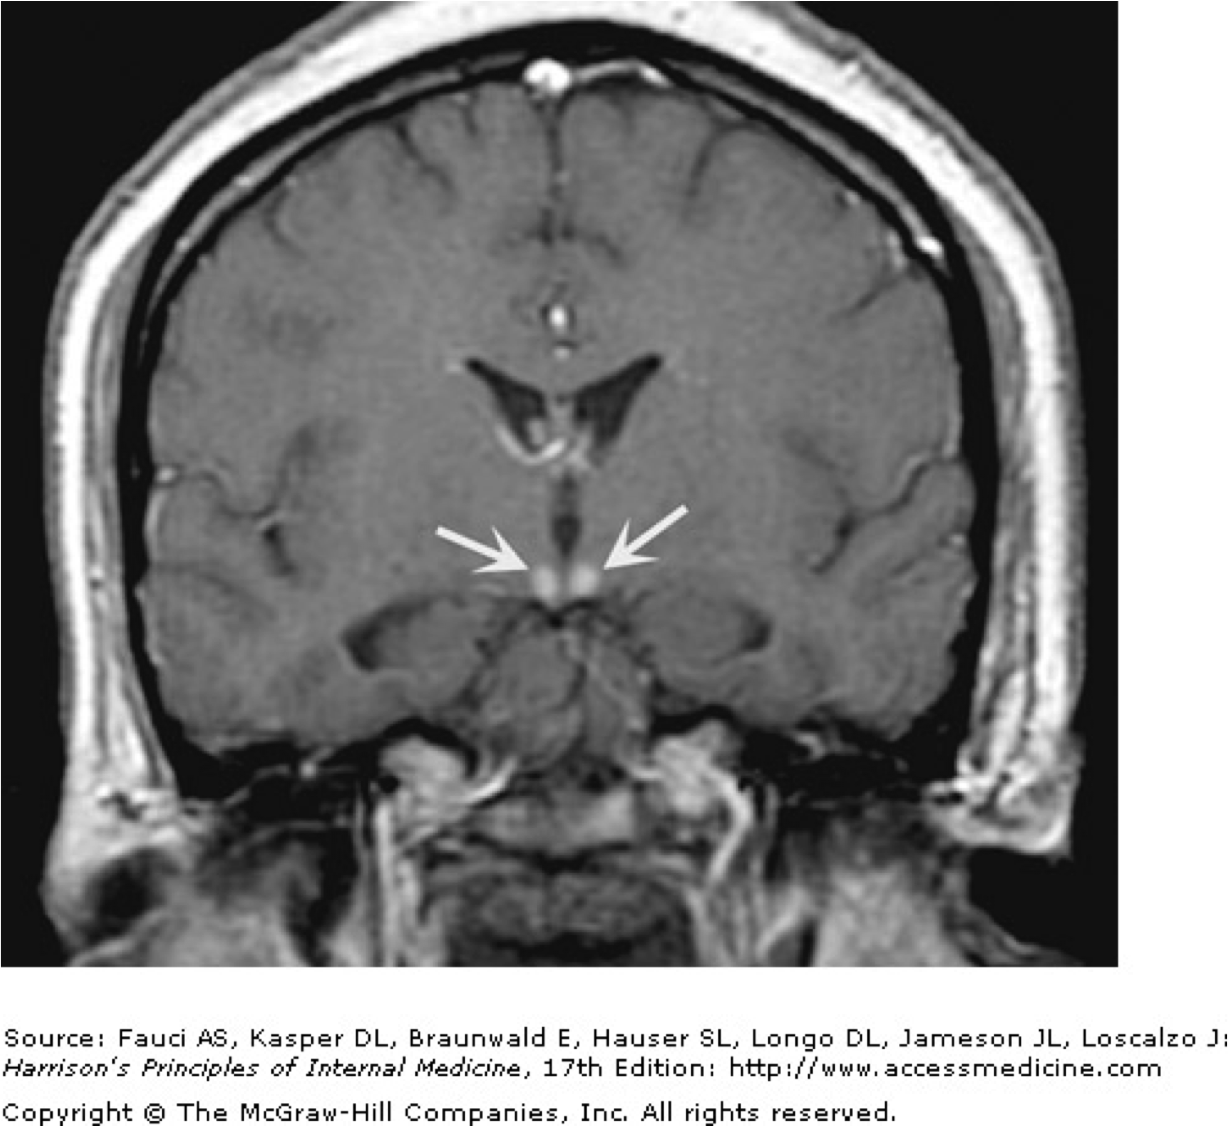

Which condition is implicated here?

Wernicke’s syndrome

mamillary bodies light up b/c of increased blood flow in this area, localizing the injected contrast